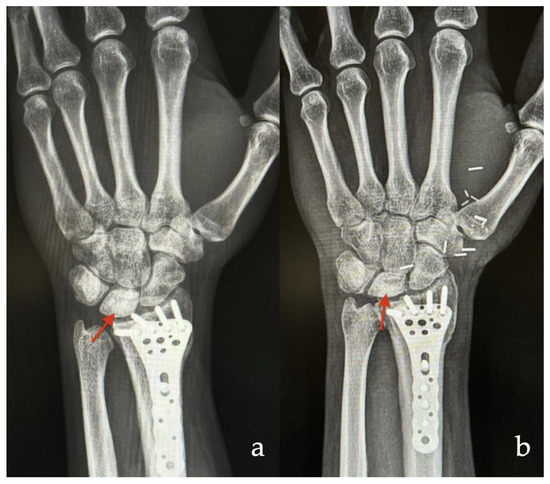

3.1.1. Case 1

| 3 | 20 | M | Lunate | Kienböck’s disease | Osteochondral | 5 |

| 4 | 40 | M | Lunate | Kienböck’s disease | Cortico-cancellous | 18 |